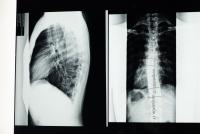

Copiii cu scolioză trebuie să lucreze la flexibilitate, întărirea și întinderea mușchilor spatelui. Mai jos vă arătăm câteva exerciții și întinderi de efectuat în cazul unor anomalii de aliniere vertebrală.